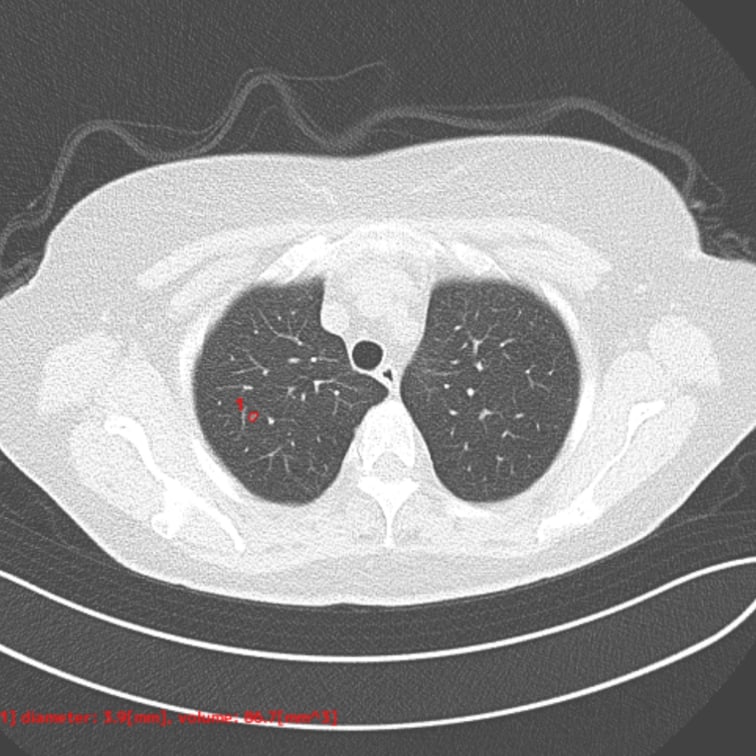

肺結節の候補領域を検出

- 肺結節候補領域検出

以下の肺結節候補領域を検出して表示します- 充実型:3mm以上30mm以下

- 部分充実型:5mm以上30mm以下

- すりガラス型:5mm以上30mm以下

- 自動計測

- 検出した候補領域の大きさ:体積 [mm³] およびAxial断面最大径 [mm] を出力

- CT値:最大・最小・平均値・標準偏差を出力

解析事例

標準線量CT